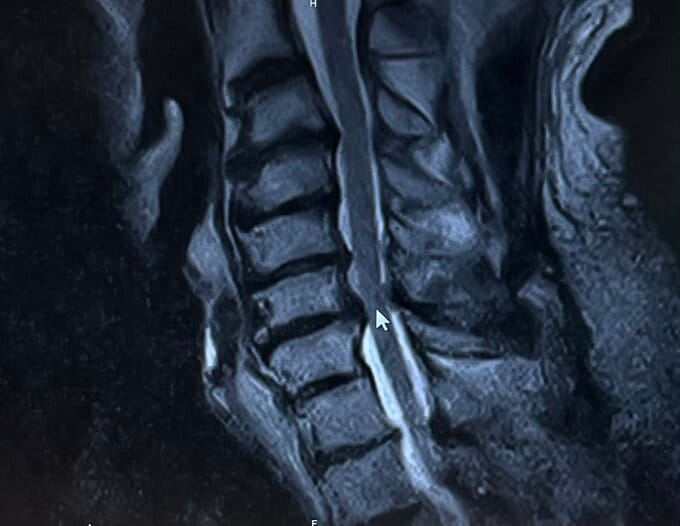

武藤さんは「右手に痺れがあったので頸椎のMRIを撮ったけど、異常はなかった。」と綴り、頸椎のMRIの画像を投稿しました。